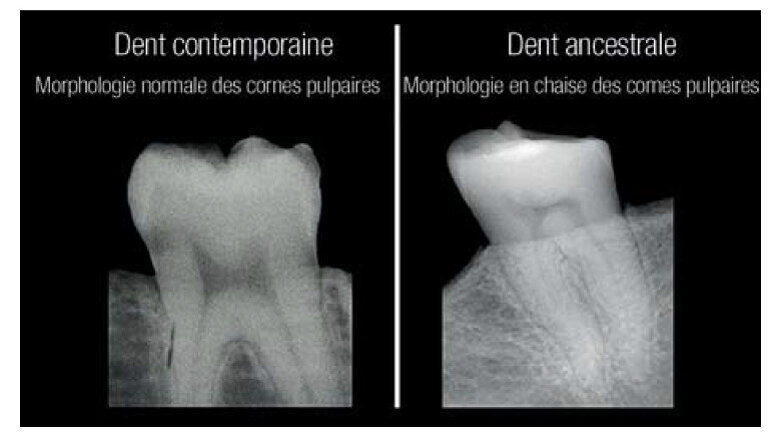

Pour éviter le gaspillage de précieux spécimens, les chercheurs se sont efforcés d’isoler les dents, aux fi ns d’une étude plus approfondie. L’utilisation de radiographies pour examiner la morphologie facilement observable des cornes pulpaires a permis aux chercheurs de mettre en évidence un motif constant et reconnaissable, qui pouvait s’avérer utile tant pour leurs études de dents ancestrales que pour des personnes susceptibles de ne pas être conscientes de leur carence en vitamine D.

Chez une personne en bonne santé, la pulpe dentaire ressemble à une arche coiffée de deux oreilles de chat. Par contre, chez une personne ayant souffert d’une carence grave en vitamine D, la pulpe a un aspect asymétrique et resserré, qui ressemble généralement à une chaise à dossier rigide.

Au terme d’une recherche précédente, D’Ortenzio et Brickley avaient évoqué l’existence de ce motif reconnaissable, et leur étude des dents ancestrales et contemporaines a confirmé que les images radiographiques sont des indicateurs invariables et fi ables d’une carence antérieure.